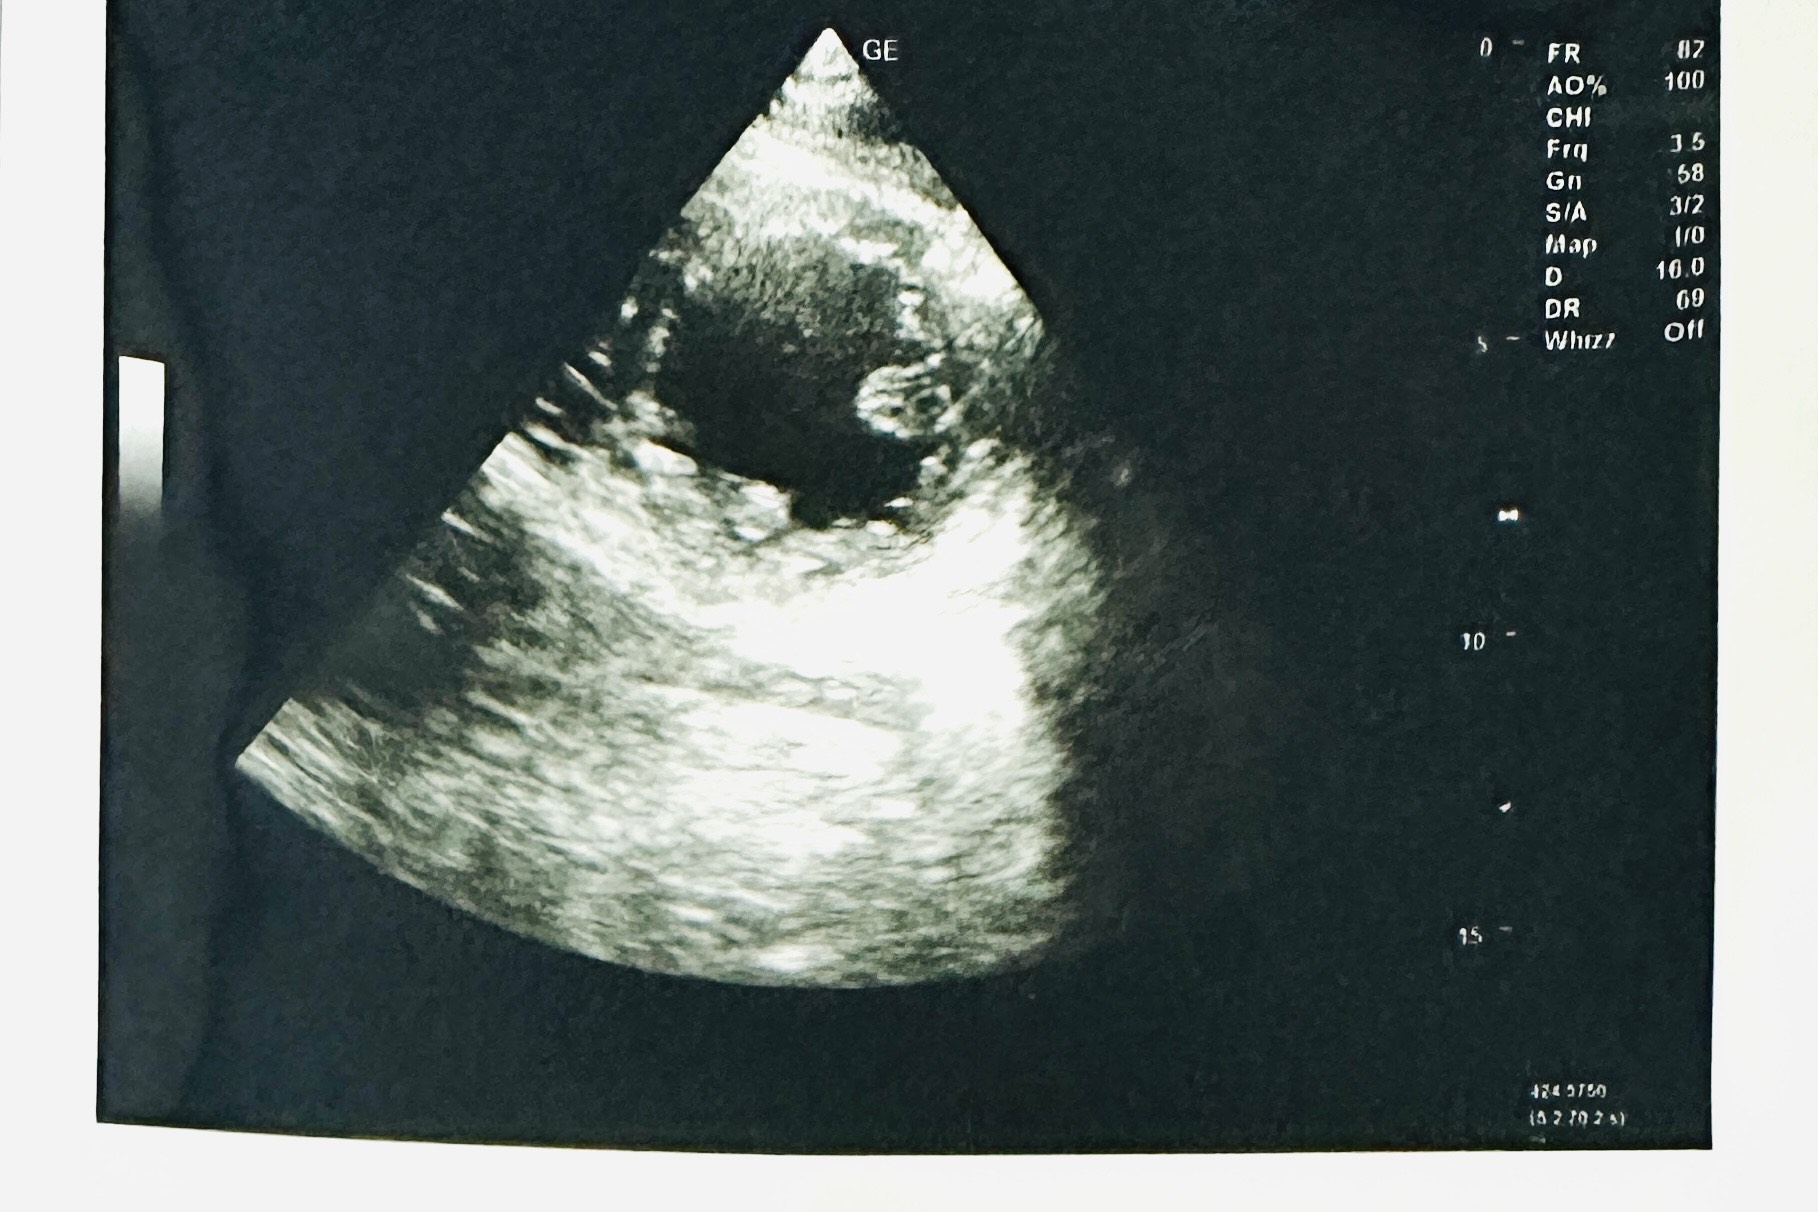

Relevant Test Results Prior to Catheterization

ECG showed Sinus Rhythm heart rate 58 bpm, ST elevation at lead II, III, aVF and Q wave in lead III, aVF and ST depression at lead I, aVL. Diagnosis of Acute ST Elevated Myocardial Infarction Inferior.Echocardiography (TTE) : Mid Inferior wall and Mid Posterior wall are severe Hypokinesia. No pericardial effusion. Primary PCI activated. Chest X ray normal.